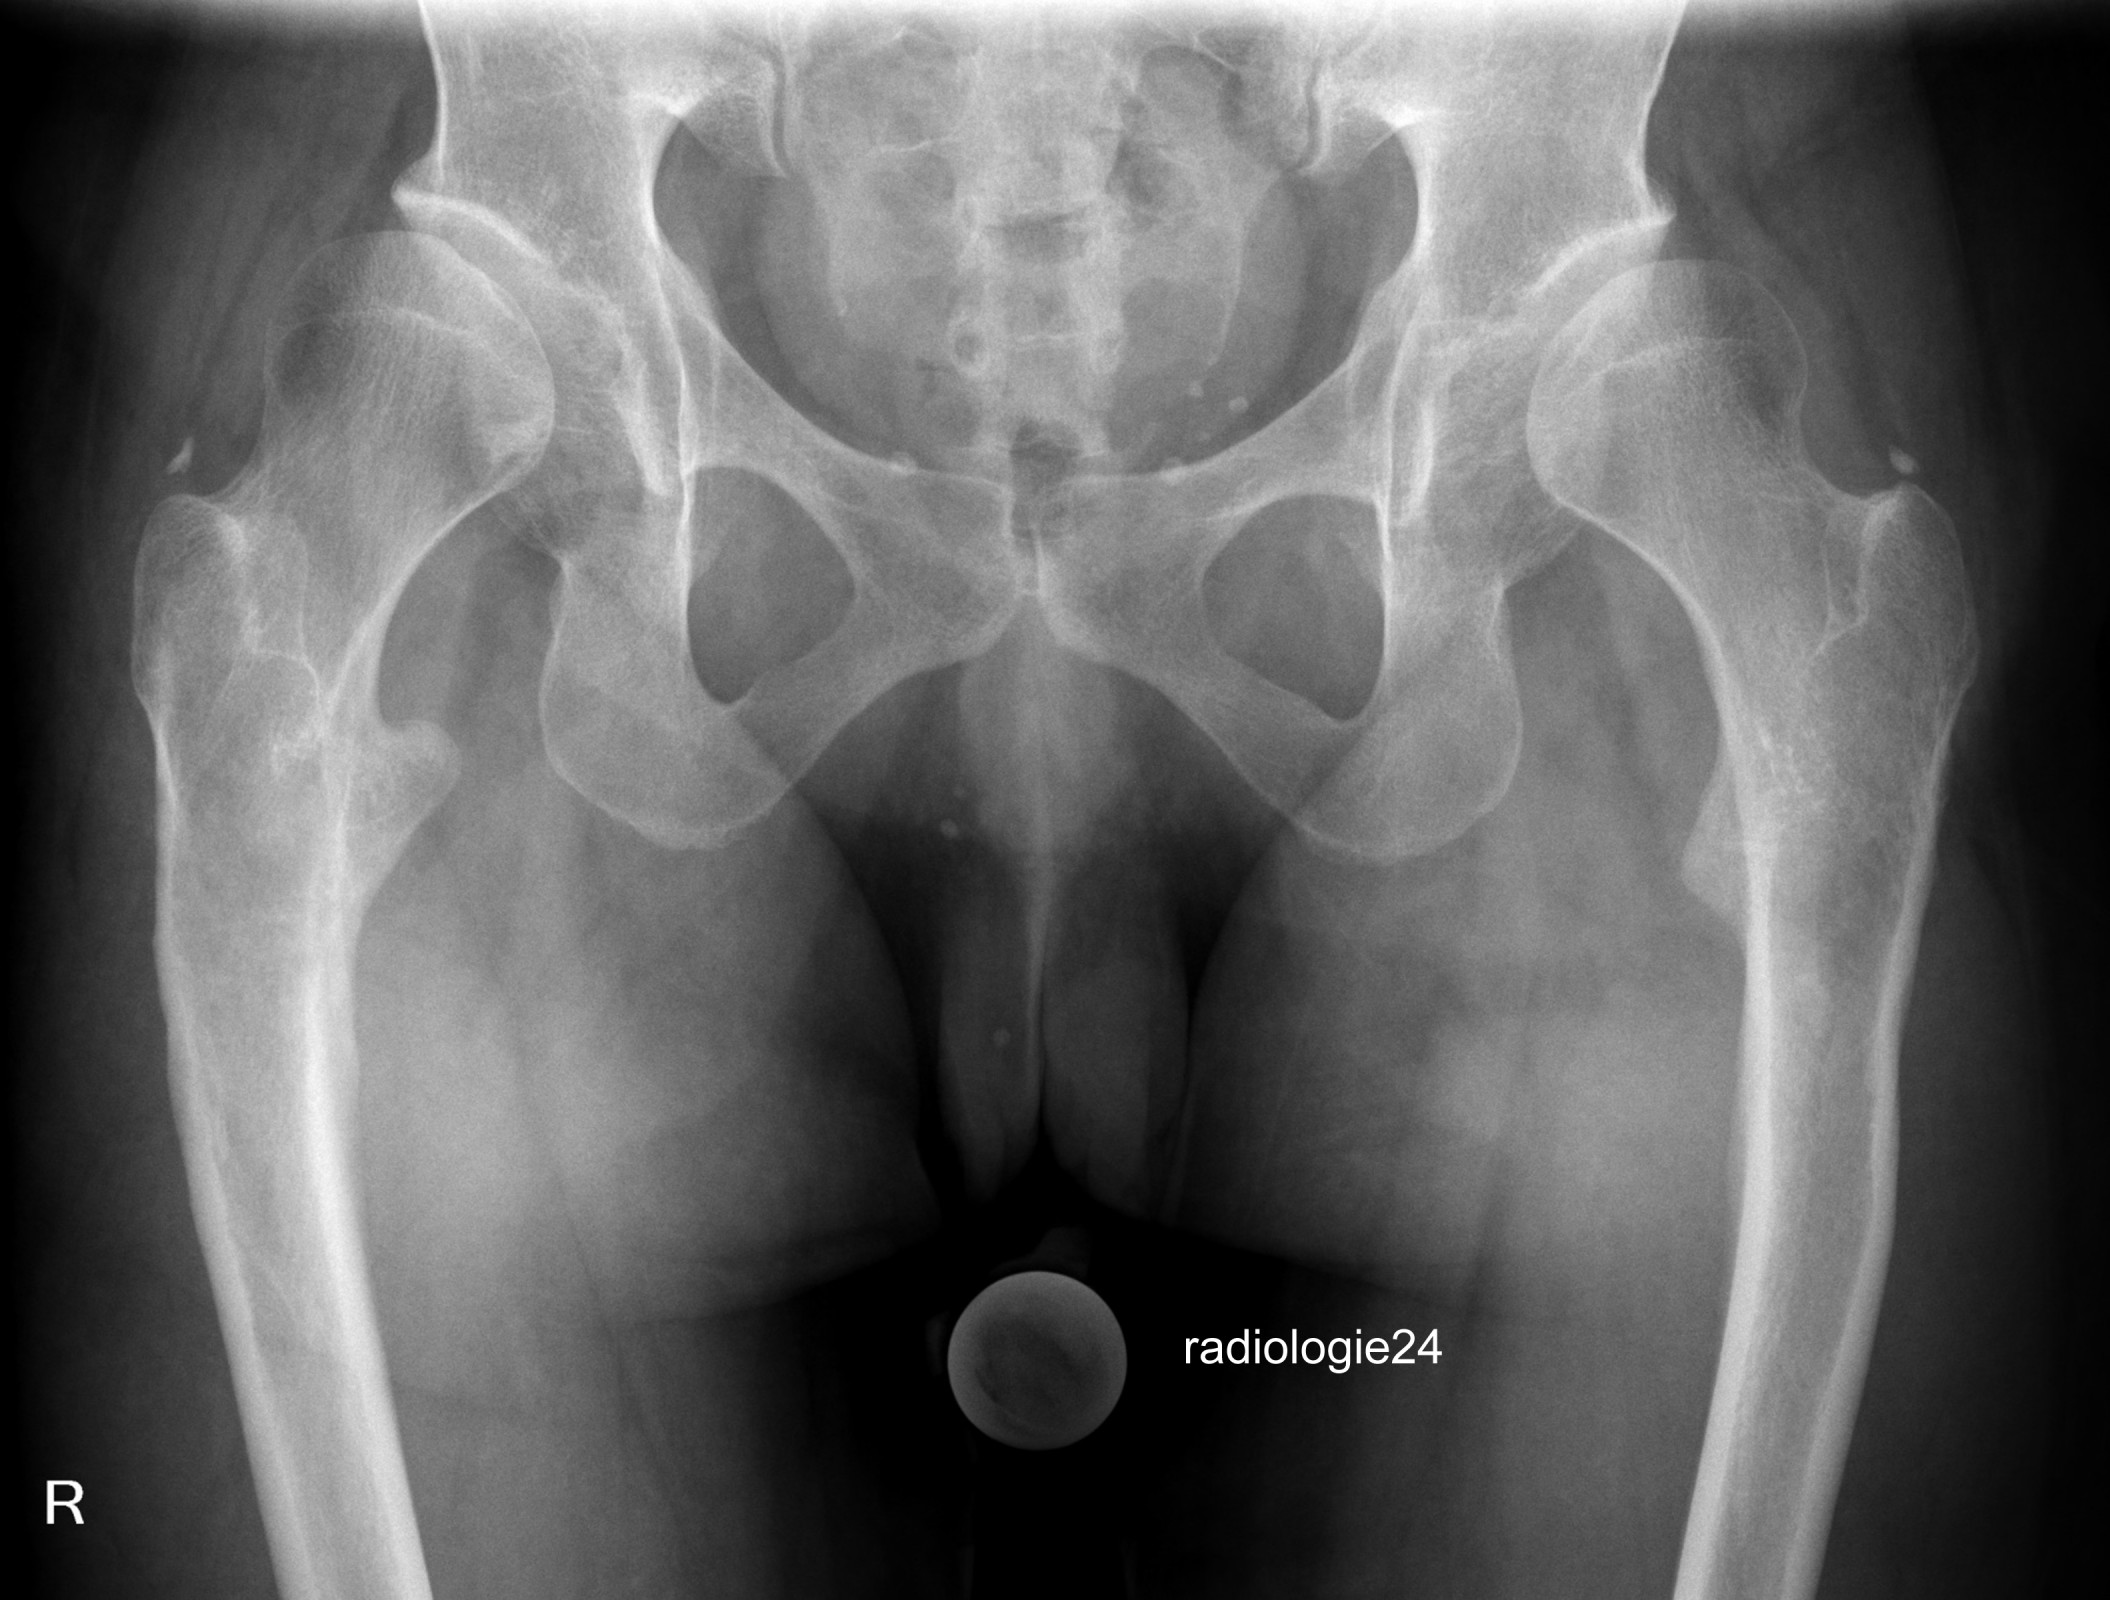

Röntgenfall des Monats Oktober 2018 mit Auflösung

34 jährige Patientin. Progrediente Schmerzen in beiden Hüftgelenken. Z.n. Sturz. Ihre Diagnose? Weitere radiologische Diagnostik notwendig?